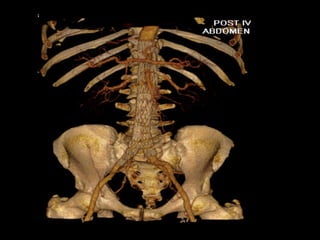

Iliac branch graftIliac branch graft

http://www.perfuse.netVascular surgery @ Tallaght